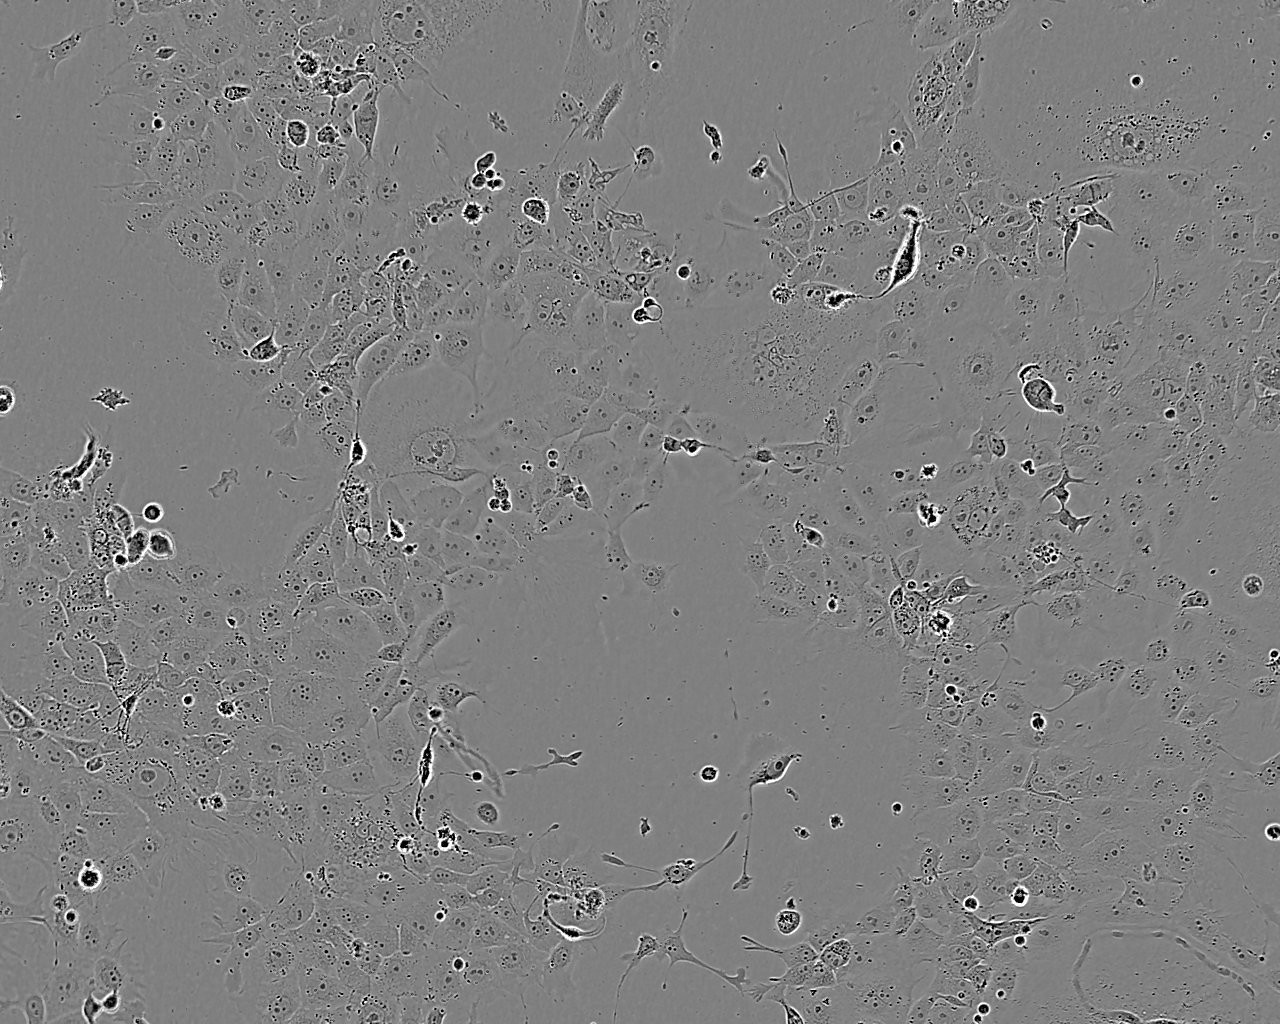

Images